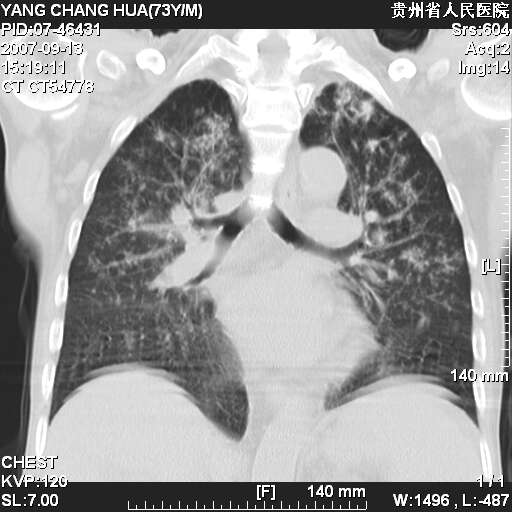

图像没有传全。肺部为感染性病灶;肺囊肿;双侧胸腔积液;肝脾肿大;腹水。

双肺部为感染性病灶.双侧胸腔积液;肝脾肿大;腹水.

双肺部为感染性病灶.双侧胸腔积液;肝脾肿大;脾脏密度不均,不除外脾侵润?腹水.

双肺点片状影,以双上肺改变明显.双侧胸腔积液.为感染性病灶,但不除外结核.

肝脾都大..

双上肺继发型肺结核。

双侧胸腔积液。

肝脾肿大。

少量腹水。

双肺散在斑片状及多发小结节状阴影,边缘模糊,双上肺野明显,双侧胸膜腔少量积液,纵隔及肺门区未见明显肿大淋巴结,肝脾肿大,脾内见多发低密度区,结合临床考虑恶性淋巴瘤(肺内表现为肺炎肺泡型),单看影像表现,肺结核不能排除。建议结合实验室检查或表浅淋巴结活检。

肺部为;恶性淋巴瘤;双侧胸腔积液;肝脾肿大;腹水。